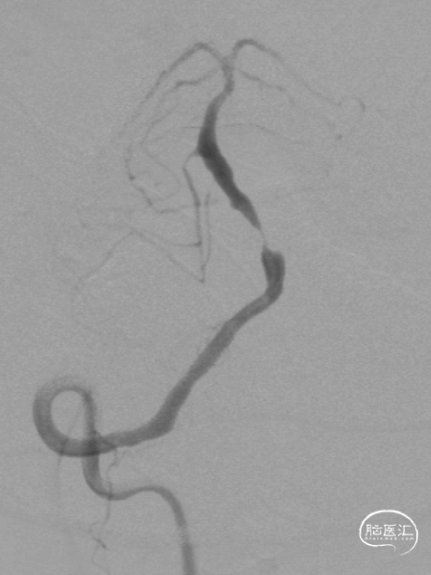

右侧桡动脉穿刺造影:右侧椎动脉优势;左侧椎动脉发自弓上,纤细迂曲;双侧后交通动脉欠发达。

半年后复查造影:支架内无明显再狭窄。椎基底动脉通畅,前向血流mTICI3级。